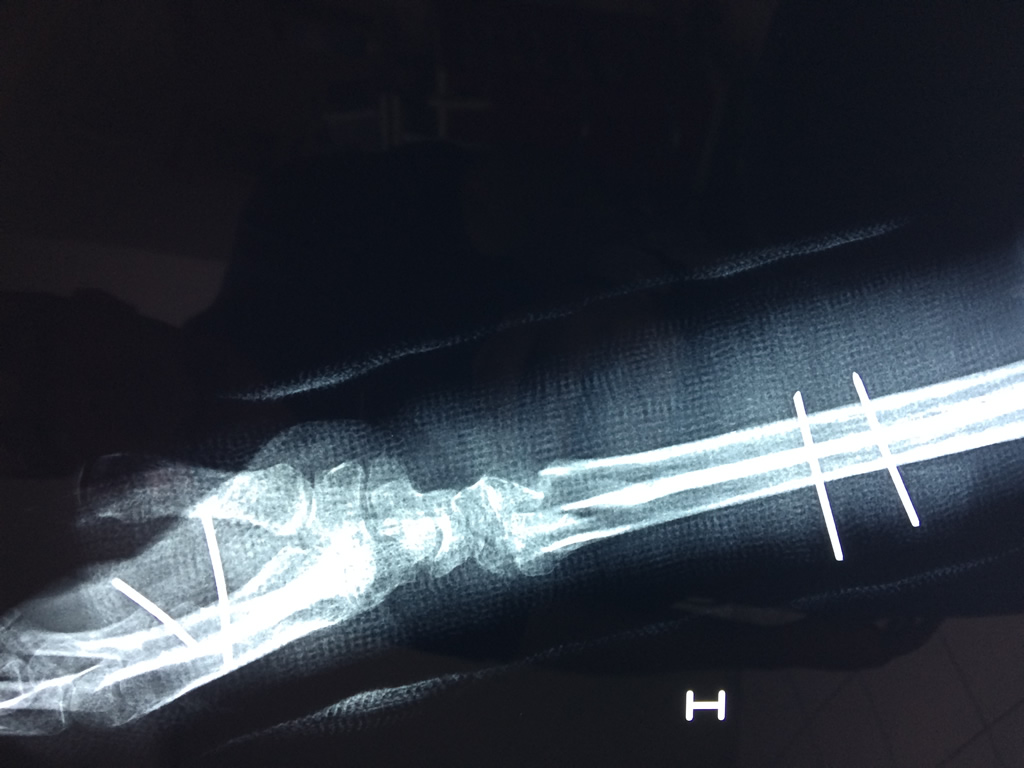

Los procedimientos más comunes en cirugía de la mano son aquellos destinados a reparar traumatismos, incluyendo lesiones de tendones, nervios, vasos sanguíneos, y articulaciones; huesos fracturados; y quemaduras, cortes, y otros daños de la piel.